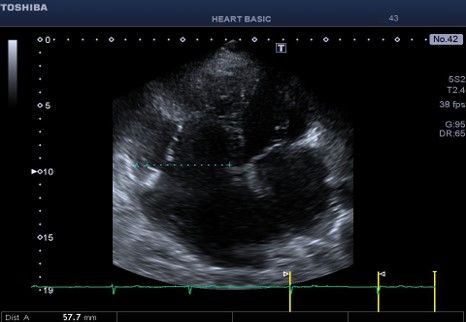

Εικόνα 1. Κορυφαία τομή 4 κοιλοτήτων εστιασμένη στη δεξιά κοιλία .

Υπάρχει σημαντική διάταση του χώρου εισόδου της δεξιάς κοιλίας (5,7

cm) και του τριχλωχινικού δακτυλίου. Ο δεξιός κόλπος είναι περί τα 200 ml.